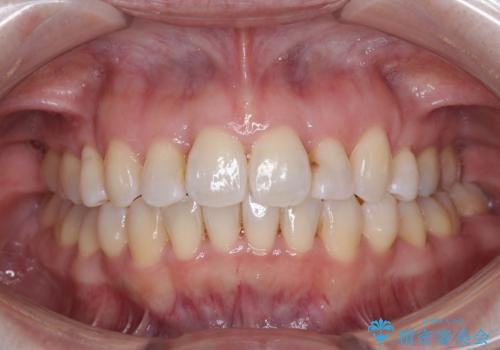

前歯のすきっ歯を治したい インビザラインによる矯正治療

- 上顎前歯の隙間を気にして来院された患者様です。

目立たない装置を希望とのことで、インビザラインを用いて矯正治療を行うこととしました。

最終的には隙間は全て閉じ、綺麗な仕上がりとなりました。